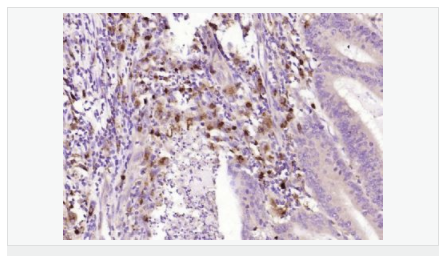

image.png